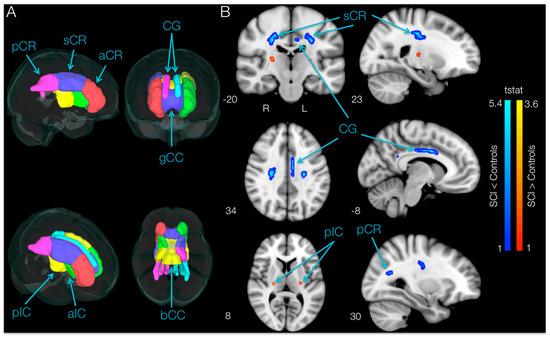

Tract-based spatial statistics (TBSS) [31], a voxel-wise statistical analysis of FA data, was used to localize brain changes. All FA maps were aligned into a common standard space using the 2-mm isotropic FA standard-space template from 58 well-aligned good quality FA images (FMRIB58_FA) as a target and the nonlinear registration tool FNIRT [32]. A mean FA skeleton was created using the mean FA image across all participants thinned at a 0.2 threshold. This skeleton represents the centers of all tracts common to the group. Each participant’s aligned FA data were projected onto this skeleton, and the resulting data were fed into a voxel-wise cross-participant statistical analysis. In order to test whether SCI and control subjects had different FA values in regions commonly associated with motor control, fourteen regions of interest (ROIs) in white matter that are commonly involved in motor control—the anterior, superior, and posterior corona radiata, the cingulum and the anterior and posterior limbs of the internal capsule for each hemisphere, as well as the body and genu of the corpus callosum—were considered in this study. A mask containing the motor ROIs (Figure 5A) was created and applied to the FA skeleton using the Johns Hopkins University International Consortium of Brain Mapping ICBM-DTI-81 white-matter atlas in FSL [33]. A two-sample t-test with 5000 permutations was used to compare the mean FA, MD, RD and AD values between SCI and control participants. Permutation testing is non-parametric [34]; therefore, assumptions of normality and homoscedasticity were not necessary.

3.4. Brain Differences in FA between SCI Subjects at Baseline and Controls (TBSS and ROI)

TBSS analysis of DTI indices within the motor areas (Figure 5A) in SCI participants compared to controls revealed areas with significantly lower (p < 0.05, uncorrected) FA values in SCI subjects bilaterally in the superior corona radiata, in the cingulum of the left hemisphere and in the posterior corona radiata of the right hemisphere. Moreover, TBSS analysis showed higher FA bilaterally in a small area of the posterior limb of the internal capsule in SCI subjects compared with controls.

ROI Results: SCI Subjects at Baseline vs. Controls

ROI analysis of white matter skeleton DTI indices within the motor areas of SCI participants revealed significantly lower (p < 0.05, uncorrected) FA values bilaterally in the anterior limb of the internal capsule (taIC_Left = 2.25, p = 0.019, 8.15% lower in SCI, and taIC_Right = 3.02, p = 0.004, 18.15% lower, respectively) when compared to controls. Lower FA values in SCI subjects on the left hemisphere occurred in the anterior corona radiata (taCR = 2.32, p = 0.016, 8.40% lower) and cingulum (tCG = 2.22, p = 0.020, 16.04% lower; Figure 5B), whereas the only region with a lower FA value in SCI subjects in the right hemisphere was the superior corona radiata (tsCR = 1.99, p = 0.032, 5.90% lower). The same regions had significantly higher MD, RD and AD. Moreover, the ROI analysis revealed no region had greater FA in SCI participants compared with controls.

Figure 5. Regions showing lower fractional anisotropy (FA) in spinal cord injury (SCI) subjects compared to controls. (A) Brain regions associated with motor function used to perform tract-based spatial statistics (TBSS) and ROI analyses; (B) TBSS results. Regions showing significantly higher (red-yellow) and lower (blue-light blue) FA values in SCI versus control subjects overlaid over the standard Montreal Neurological Institute (MNI)152 T1-weighted anatomical scan (p < 0.05, uncorrected). The location of each slice in Montreal Neurological Institute space is shown at the lower left section. a-s-pCR, anterior, superior and posterior corona radiata; CG, cingulum; g-bCC, genu and body of corpus callosum; a-pIC, anterior and posterior limbs of internal capsule.